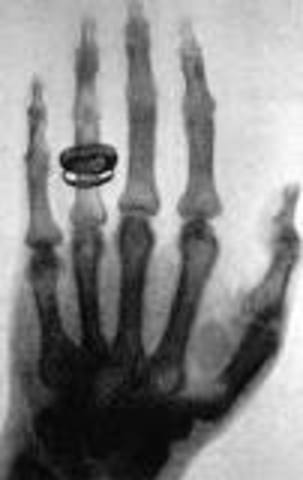

• rayos x

rayos x

El físico alemán Wilhelm Conrad Röntgen descubrió los rayos X en 1895, mientras experimentaba con los tubos de Hittorff-Crookes y la bobina de Ruhmkorff para investigar la fluorescencia violeta que producían los rayos catódicos.